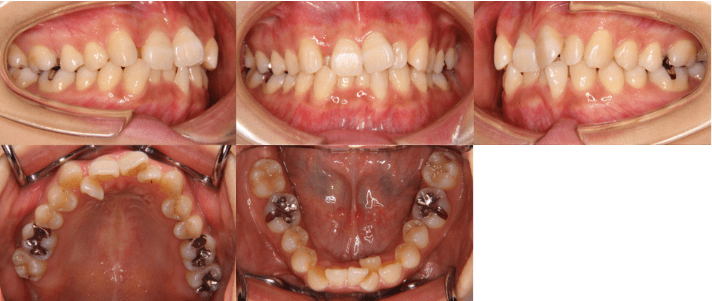

<治療前>

| 初診時年齢 | 25歳7ヶ月 |

| 主訴 | 前歯のガタガタ |

| 診断 | 交叉咬合を伴う叢生症例 |

| 治療内容 | 小臼歯4本を抜歯した後、インビザラインを使用して主訴である叢生の改善を行いました。 |

| 治療期間 | 2年 |

| リスク | 矯正治療による歯の移動に伴う痛み、歯根吸収、虫歯 |

| 費用 | 80万円 |